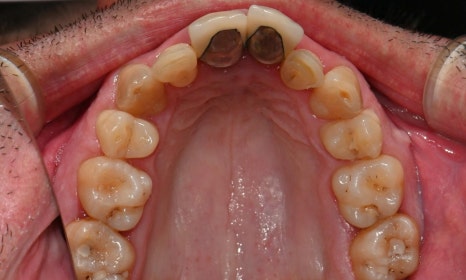

이 환자분은 영국에서 오신 40대 초반 남성분으로, 선천적으로 턱이 작아 어린 시절 턱을 앞으로 이동시키는 악교정 수술과 함께 약 6년 간 치아 교정을 받으셨다고 하셨습니다. 그러나 교정 치료가 충분히 만족스럽게 이루어지지 않았고, 이후 사고로 앞니를 다쳐 보철 치료를 받게 되었습니다. 시간이 지나면서 잇몸이 퇴축되어 앞니 보철물의 금속 부분이 노출되었으며, 제 2급 부정교합 및 불규칙한 치아 배열로 인해 심미적으로 정돈되지 못한 상태로 오랜 기간 지내오셨습니다. 이제는 앞니를 보다 아름답게 개선하고 싶다는 바람으로, 멀리 영국에서 한국까지 내원해 주셨습니다.

2025-11-28 초진 : 연세정원치과

진단 결과, 교합시 하악 전치가 거의 보이지 않을 정도로 깊은 교합을 보이고 있었으며, 어린 시절 외상을 입었던 앞니는 치아 뿌리 부근에 광범위한 염증이 관찰되어 장기적인 유지가 어려운 상태였습니다. 이에 앞니 두 개는 발치를 결정하였고, 환자의 비교적 젊은 나이를 고려하여 가능한 한 최대한 치아를 보존하기 위해 앞니 부위 임플란트를 고려했습니다. 그러나 해당 부위 골 손실이 매우 심했고, 외국인 환자로 장기간 내원이 어려운 상황이었기 때문에, 광범위한 골이식을 동반한 임플란트 치료 보다는 비교적 짧은 기간 내에 기능과 심미를 회복할 수 있는 브릿지 보철 치료를 계획하였습니다.